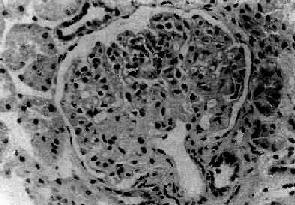

图12-21 局灶性节段性肾小球硬化 肾小球毛细血管丛的一段硬化,玻璃样变 病变继续发展,受累的肾小球逐渐增多。有些肾小球毛细血管丛可全部纤维化、硬化、玻璃样变(球性硬化)。相应的肾小管也萎缩、纤维化。肾间质纤维组织增生,有少量淋巴细胞和单核细胞浸润,有时并可见泡沫细胞聚积。晚期,大量肾小球硬化可发展为弥漫性硬化性肾小球肾炎而导致肾功能不全。 【临床病理联系和结局】 局灶性节段性肾小球硬化病人约80%表现为肾病综合征。但与一般肾病综合征不同,其中约2/3同时伴有血尿,并常有高血压。大量蛋白尿,多为非选择性。病人对激素治疗效果不好,有效率仅为20%~30%。病变为进行性,常继续发展,可导致肾功能不全。一般儿童预后比成年人好。

七、局灶性节段性肾小球硬化局灶性节段性肾小球硬化(focal segmental glomeralosclerosis)病变为局灶性,节段性,仅累及少数或部分肾小球。病变的肾小球毛细血管丛呈节段性硬化,是引起肾病综合征常见的原因之一。多见于儿童和青年人。此型肾炎病变为进行性,病人对激素治疗效果不理想。多继续发展为弥漫性硬化性肾小球肾炎。 【病理变化】 病变为局灶性,往往从肾皮质深部近髓质部分的少数肾小球开始。早期仅少数肾小球受累,其他肾小球无明显病变或病变轻微。病变的肾小球毛细血管丛的部分毛细血管萎陷,系膜增宽、硬化、玻璃样变(图12-21)。系膜内和毛细血管内常有脂滴和玻璃样物质沉积。有时可见吞噬脂类的泡沫细胞聚积。电镜下可见硬化部分毛细血管基底膜皱缩,厚薄不均匀。其间可见电子致密物和脂滴沉积。上皮细胞足突消失。免疫荧光检查可见病变肾小球内有免疫球蛋白和补体沉积,主要为IgM和C3。